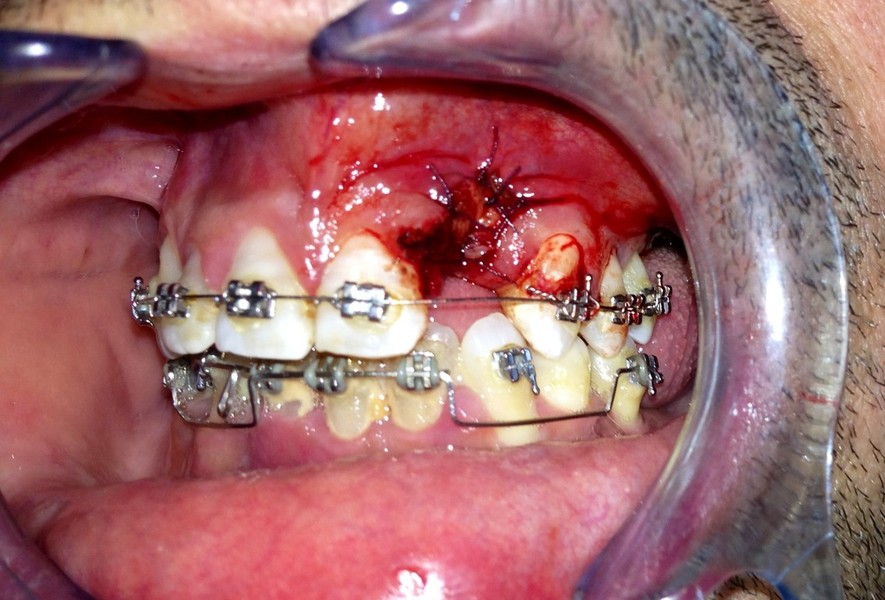

Implantologia avanzata con contestuale rimozione impianti e cisti

Video di una Parte dell'intervento in cui si puo' vedere la comunicazione tra impianti rimossi e pavimento nasale.

Estrazione di un canino incluso e contestuale inserimenti di impianto e innesto osso eterologo